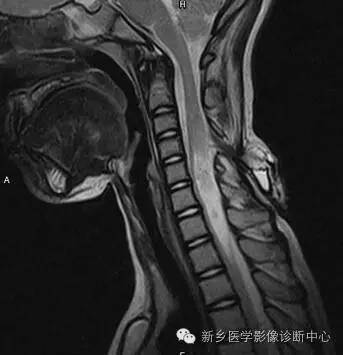

MR:

脊膜膨出:囊性肿块,与鞘膜囊想通;

脊髓脊膜膨出:囊性肿块内见脊髓或神经;

合并脊髓空洞,椎管脂肪瘤,脊髓低位,脊髓栓系,终丝粘连